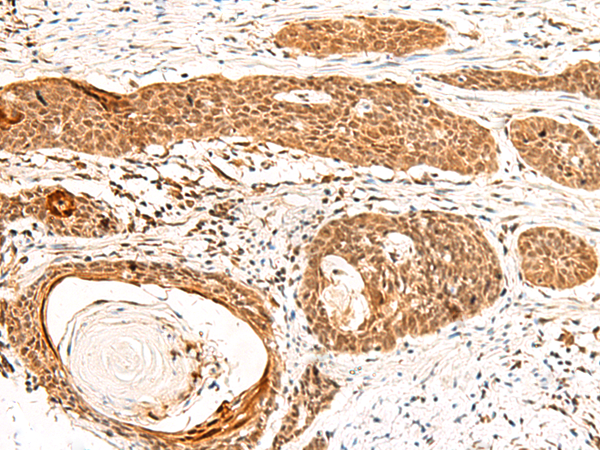

分类: 科研抗体货号: P13578别名: SS1; DRB1; HLA-DRB; HLA-DR1B应用: IHC反应种属: Human